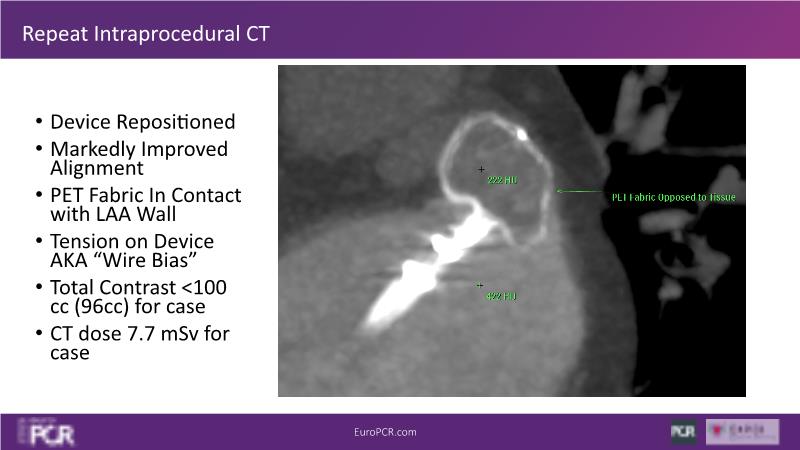

Explore this session to discover the latest innovations in interventional cardiology images, including the benefits of artificial intelligence and angio-CT in PCI/SHD procedures. Learn about Alphenix Evolve and the initial experiences with AI imaging in daily cathlab practice, alongside intraprocedural angio-CT guided LAAO, and engage in discussions on meaningful tools that can transform patient care.